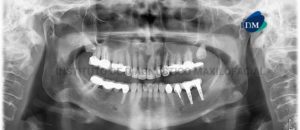

Paciente femenino de 55 años de edad, es referido al Instituto de Diagnóstico Maxilofacial (IDM) para evaluación integral. En la radiografía panorámica (Figura 1) se